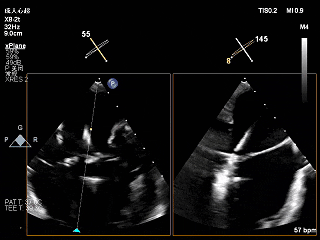

夹子关紧后上彩

夹子关小后3D观察组织桥

夹子关小后3D上彩

反流降至轻度

夹子释放后,2D下color,反流降至轻度

夹子释放后3D下观察组织桥稳定,反流降至trace

夹子释放后压差为2mmHg

肺静脉逆流明显改善